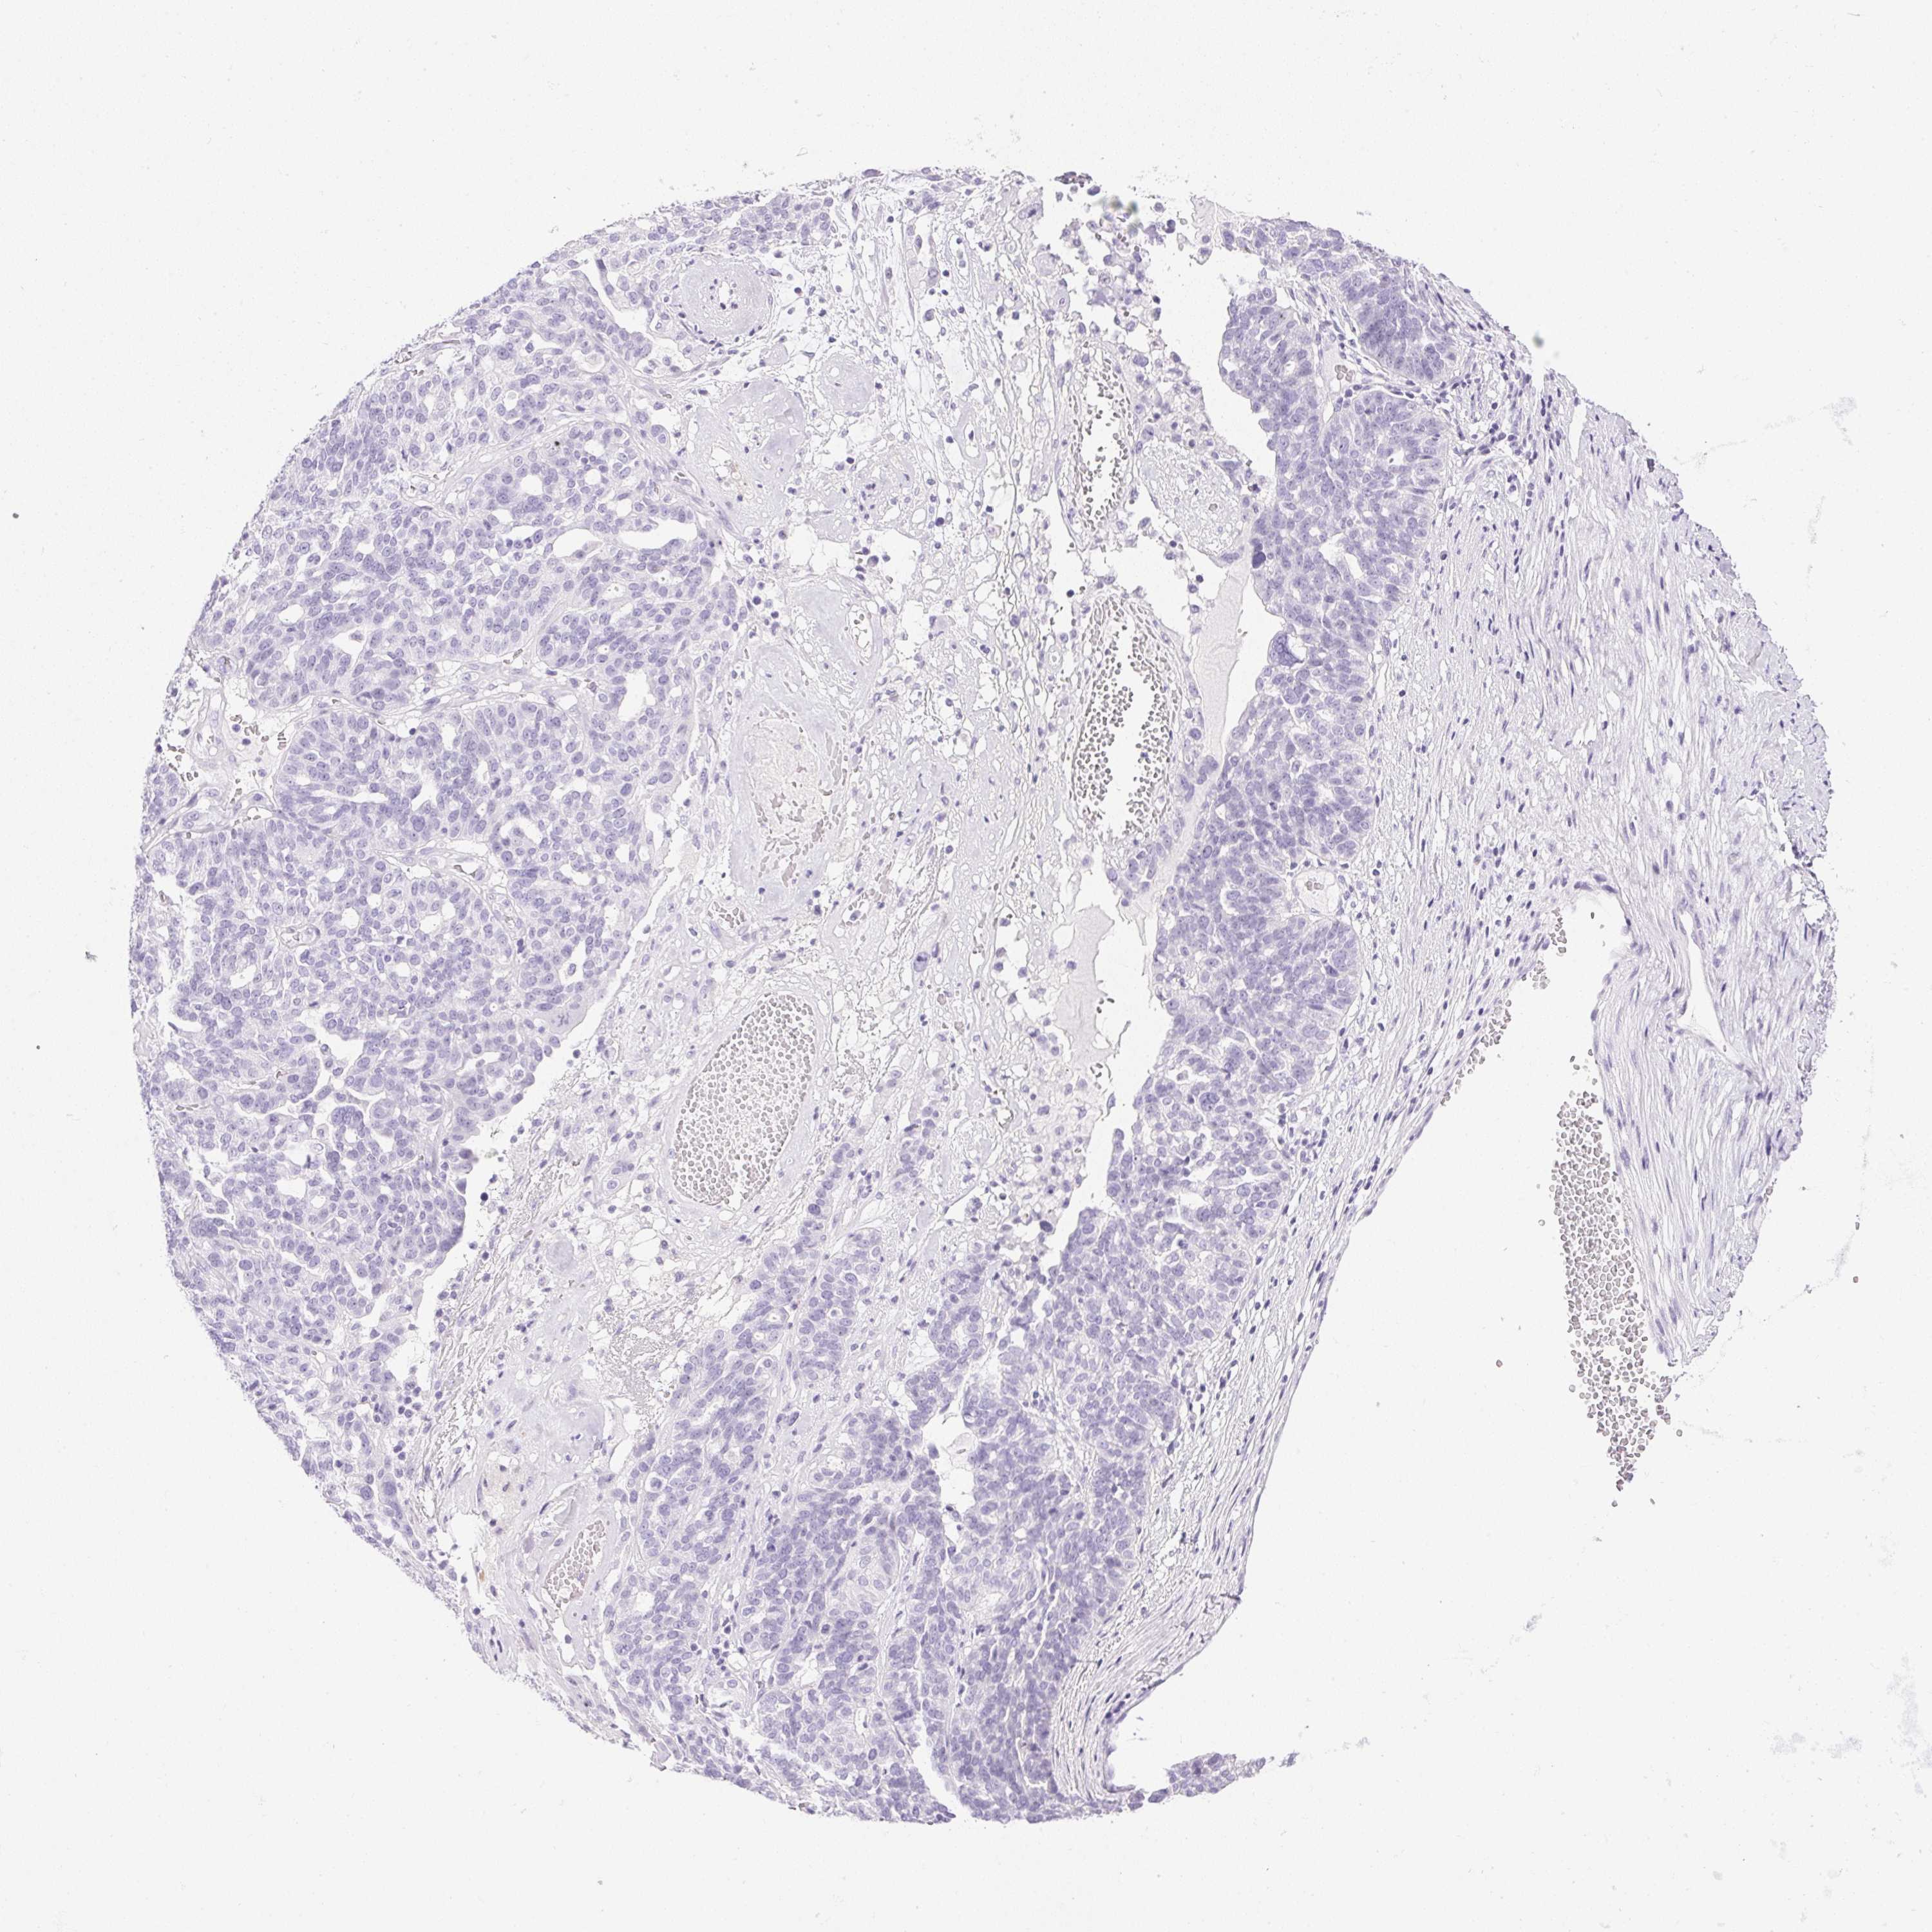

OVARIAN CANCER - Protein expressioni

A mouse-over function shows sample information and annotation data. Click on an image to view it in a full screen mode. Samples can be filtered based on level of antibody staining by selecting one or several of the following categories: high, medium, low and not detected. The assay and annotation is described here.

Note that samples used for immunohistochemistry by the Human Protein Atlas do not correspond to samples in the TCGA dataset.

Antibody stainingi

Antibody staining in the annotated cell types in the current human tissue is reported as not detected, low, medium, or high, based on conventional immunohistochemistry profiling in selected tissues. This score is based on the combination of the staining intensity and fraction of stained cells.

Each image is clickable and will lead to virtual microscopy that enables deeper exploration of all samples and also displays staining intensity scores, fraction scores and subcellular localization as well as patient and tissue information for each sample.

Antibody HPA038069

Antibody HPA046340

Antibody CAB026158

Cystadenocarcinoma, serous, NOS

Carcinoma, endometroid

Cystadenocarcinoma, mucinous, NOS

Carcinoma, NOS